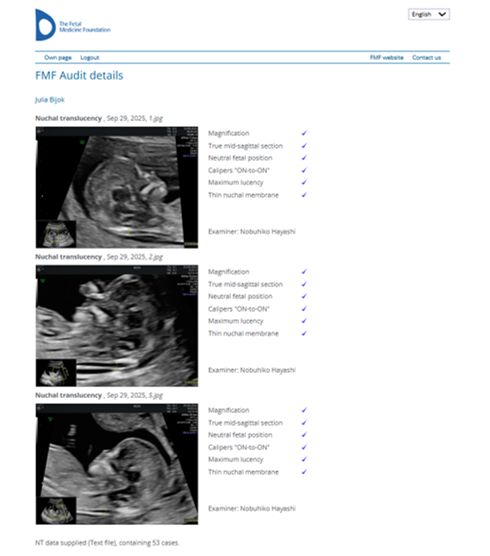

The Fetal Medicine Foundation (FMF) nr 84981 – uprawniający do wykonywania badań prenatalnych z wyliczeniem ryzyka aberracji chromosomowych u płodu,